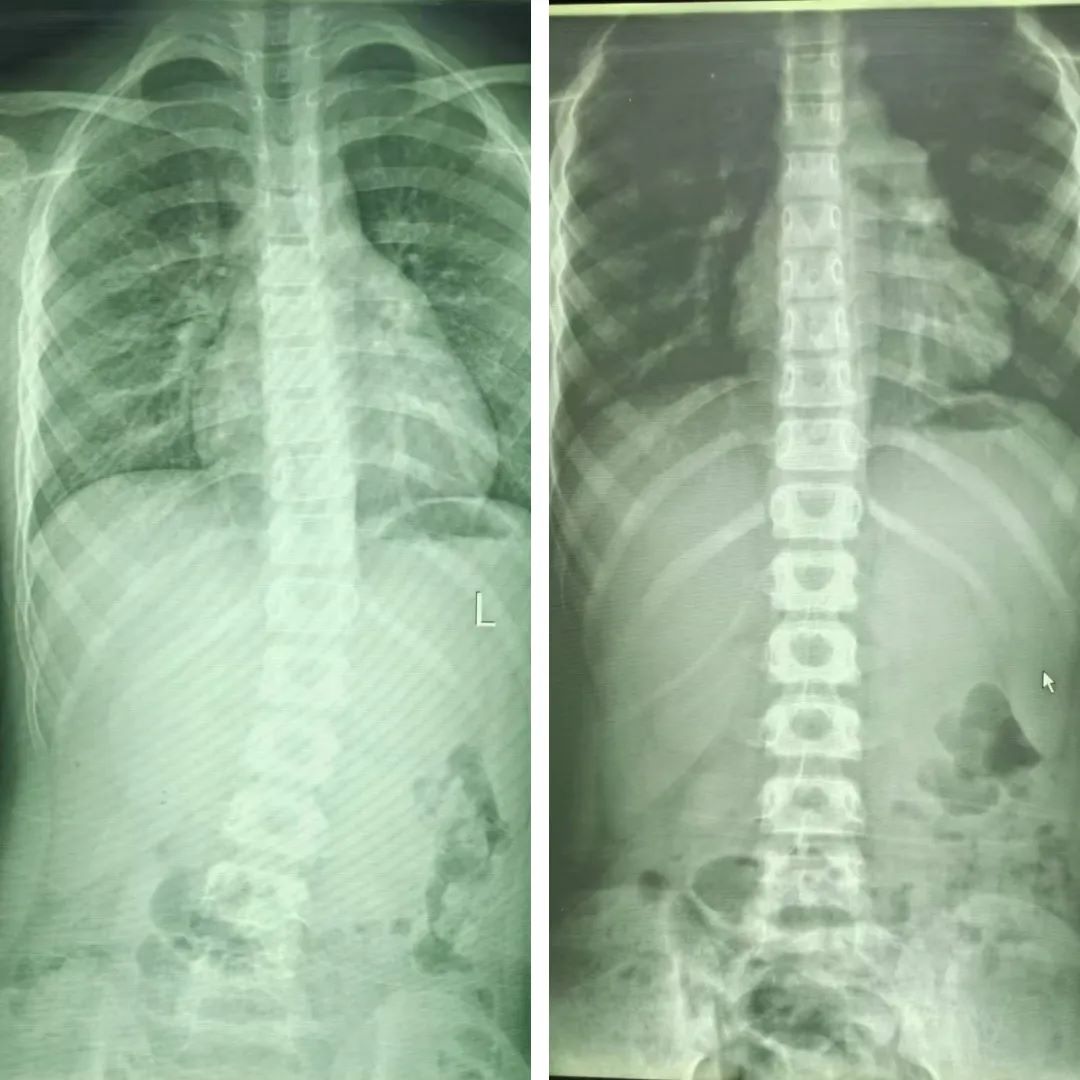

▲治疗前后对比

在家人的悉心督促和陪伴下,仅仅一个月的时间,晗晗的脊柱恢复到了正常状态。